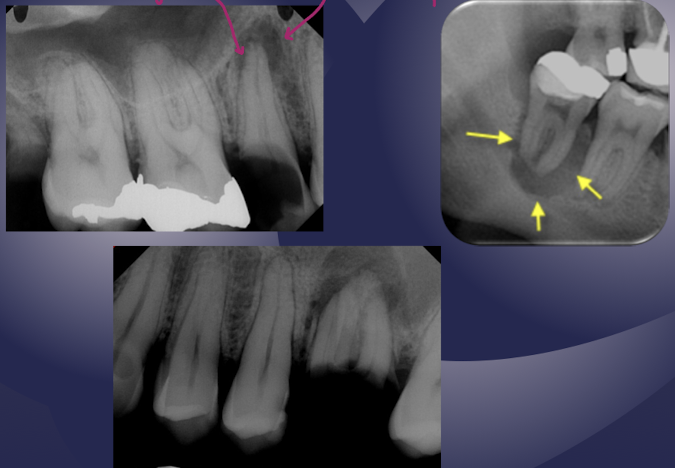

what are other terms for sclerosing osteitis?

focal sclerosing osteitis, condensing osteitisÂ

hardening of the bone; bone deposition increase in radiopacity of bone (plus widened PDL)

sclerosing osteitisÂ

sclerosing osteitis

bone deposition around area of rarefaction

sclerosing osteitis + radiolucency

what are the alterations in trabecular bone pattern and marrow spaces of periapical inflammatory diseases?

thicker trabeculae and increase in numberÂ

what are some effects of periapical inflammatory disease on surrounding structures?

bone deposition

alteration in trabecular bone pattern and marrow spaces

periosteal new bone formation

perforation of bone border

halo sign

elevation/displacement of floor f maxillary sinus

maxillary posterior teethÂ

periostitis/onion skin

periostitis, onion skin

periosteal bone formation in floor of maxillary sinus

periostitis and mucositisÂ

mucosal thickeningÂ

mixture of rarefying and sclerosing osteitis

no pathology, submandibular gland fossa

dense bone island of vital tooth, no widening of PDL; inositiosis just extra bone w/in two plates of cortical bone